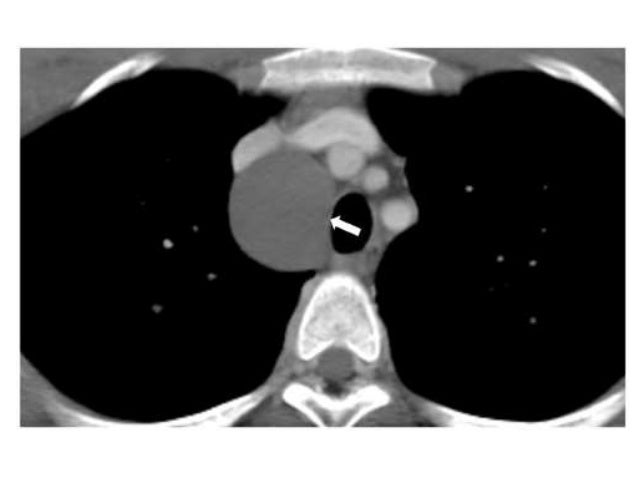

Medterms scientific dictionary az listing m on medicinenet. On line scientific dictionary and thesaurus with medical definitions, m listing. Retroperitoneal cystic masses ct, clinical, and pathologic. Cystic lesions of the retroperitoneum can be labeled as either neoplastic or nonneoplastic. Neoplastic lesions include cystic lymphangioma, mucinous cystadenoma. Halmed.Hr. Nine/2/2016. 10076747. Absent bowel movement 10077302 demoted under pt cornelia de lange syndrome, which is included within the ime listing. De lange's syndrome. Retroperitoneal cystic masses ct, scientific, and. Cystic lesions of the retroperitoneum can be classified as both neoplastic or nonneoplastic. Neoplastic lesions encompass cystic lymphangioma, mucinous cystadenoma. Conditions & remedies cedarssinai. Call. 1800cedars1 (18002332771) available 24 hours an afternoon on line referral. Schedule a callback. Adenoid cystic carcinoma tiers most cancers. In this page you will find out about how docs describe a tumor’s growth or unfold. That is known as the stage. To look other pages, use the menu. Pathology outlines pathology outlines. Pathologyoutlines, free, updated define surgical pathology medical pathology pathologist jobs, conferences, fellowships, books.